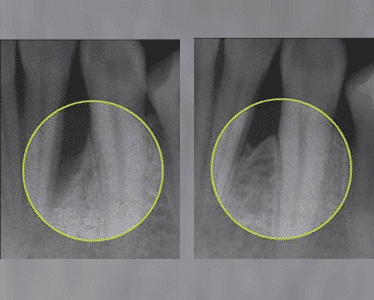

The efficacy of Emdogain™ in the treatment of localised bone loss caused by periodontitis has been scientifically verified. It can also promote the healing of gum grafts.

With Emdogain™ it is possible to reliably regenerate bone lost due to periodontitis, helping to preserve strong teeth